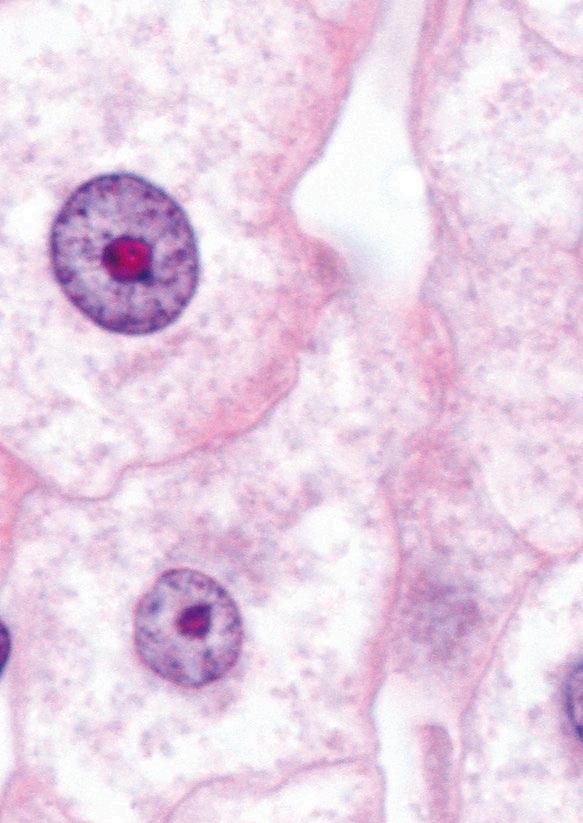

They are secondary metabolites of certain fungi (genera Aspergillus, Penicillium, Fusarium, Alternaria, and Claviceps)[1] and are produced before harvest of grains (fungi as plant pathogens), or during storage (fungi growing saprophytically).

AFs are produced mainly by Aspergillus flavus, A. parasiticus and A. nomius and are detected usually in maize, peanuts and cottonseed.

AFs and, in particular, AFB1 are considered the most potent naturally occurring carcinogens. AFB1 is metabolised predominantly in the liver by a number of cytochrome P450 enzymes, generating several hydroxymetabolites, such as AFM1, AFQ1 and AFP1 and two significantly reactive epoxides, AFB1 exo-8,9-epoxide and AFB1 endo-8,9-epoxide[20-22] .

The exo-epoxide interacts with the guanine part of DNA, resulting in the formation of AFB0-guanine adducts such as AF-N7-Gua which can be used (in urine) as a biomarker of exposure[20,21,23]

Both the endo- and exo-epoxide of AFB1 are toxic and lead to the formation of aflatoxin–albumin (AF-alb) in hepatocytes, which are observable in the sera of exposed animals and humans[20]. These albumin adducts of AFs have been discussed as useful biomarkers of AFs-induced hepatotoxicity[20]

Aspergillus species mainly, and Penicillium species can produce ochratoxins with OTA having major nephrotoxic properties.